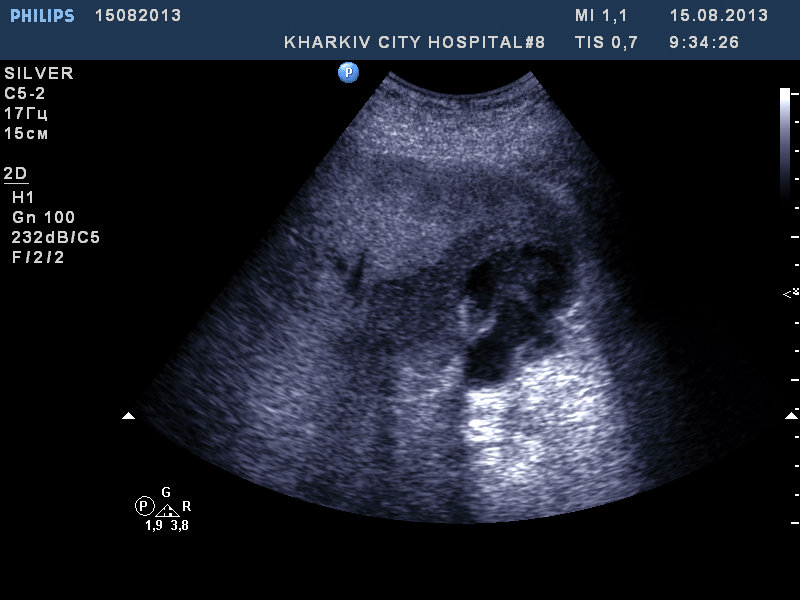

Пациент 63 лет. доставлен в клинику с фибр.предсердий. Ритм восстановили. Температура до 40 (свечками). сОЭ 60 .Жалобы на тупую разлитую боль в правом подреберье.

При проведении узи:

Желчный пузырь типично расположен, деформирован, неровный нечеткий контур. Неоднородное содержимое. Конкремент в полости не лоцируется. У желчного пузыря множественные гипоэхогенные участки неровной формы с наличием жидкостного компонента.

Расцениваю как признаки острого холецистита, признаки перфорации желчного пузыря, признаки подпеченочного абсцесса. Нельзя исключить холедохолитиаз.

Соглашусь, похоже на острый деструктивный холецистит, паравезикальный абсцесс. Четко видна дыра в стенке пузыря.

Кстати, не вижу камней в пузыре, - как вариант - деструкция/некроз ж. пузыря вследствие тромбоза пузырной артерии, подпеченочный абсцесс.

Но стратегически это ничего не меняет.